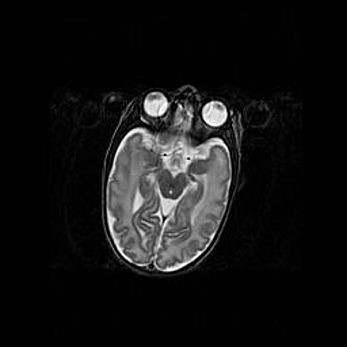

Сообщающаяся гидроцефалия. Кистозная энцефаломаляция головного мозга.

Возраст: 3 месяца 4 дня

Вес: 3100 г

Пол: женский

Окружность головы: 34 см

Срок гестации: 31 неделя

Кистозная энцефаломаляция головного мозга - одна из форм поражения головного мозга в детском возрасте. Характеризуется возникновением множественных и распространённых кист в коре, белом веществе и подкорковых образованиях головного мозга у плодов, новорождённых и детей раннего возраста. Развитие кистозной энцефаломаляции связано с внутриутробной асфиксией и гипотонией, родовой травмой, тромбозом синусов, пороками развития сосудов, инфекциями, сепсисом и другими причинами. Наиболее значимые инфекционные агенты: вирусы простого герпеса, цитомегалии, краснухи, токсоплазмы, энтеробактерии, золотистый стафилококк и другие.